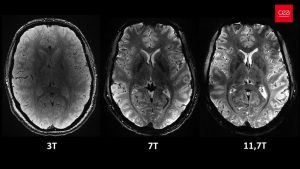

به گزارش دانشجو قدرتمندترین دستگاه MRI جهان، اولین اسکن خود از مغز انسان زنده را به ثبت رساند. این اسکن...